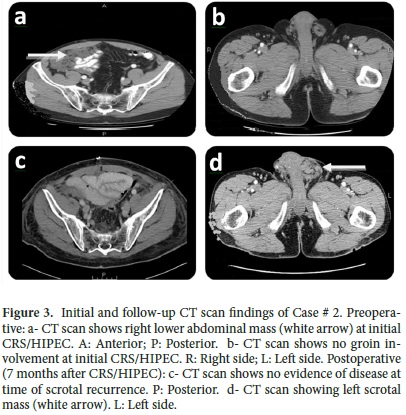

Five months after the herniorrhaphy, the patient was referred to our Institution with a complaint of right lower abdominal discomfort. Further evaluation with a CT scan showed diffuse peritoneal metastases (Fig. 3a). No groin disease was found on physical examination or CT scan (Fig. 3b). Three weeks later, the patient underwent a CRS/HIPEC for DPAM. The pre/post surgical PCI was 36/0 and a CC-0 was achieved. Hyperthermic intraperitoneal chemotherapy (closed technique) was carried out by using 40 mg of Mitomycin-C for 90 min (30 mg given at time 0 and 10 mg 30 min later) with inflow temperature maintained at 43° C and outflow temperature of 41-42° C. Seven months later, on follow up, the patient presented with left groin discomfort and a scrotal mass. A CT scan identified no evidence of intra-abdominal disease (Fig. 3c) and a left scrotal mass (Fig. 3d). Fine-needle aspiration determined the existence of mucin in the left scrotum. Two months later, the patient had CRS including left orchiectomy, removal of in-situ Prolene® mesh, HCS (Fig. 1), and subsequent repair of inguinal defect with Prolene® mesh. Complete cytoreduction was achieved at this stage. The patient was discharged on post-operative day 3 without complication. On follow-up, the patient is considered NED at 57 months after his initial CRS/HIPEC and 32 months post CRS/HCS.